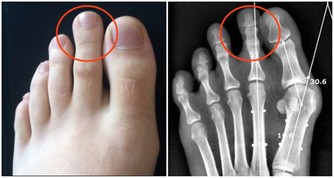

肝癌引起右肩部疼痛就是牽涉痛,

這可能是肝癌壓迫附件的膈肌或肺部以下的肌肉神經所引起的。

當肝臟腫瘤逐步增大,有可能會壓迫附近的橫膈膜,亦可壓著肺部以下的肌肉神經。

而這些被壓著的神經正好是連接右肩的神經,就會引發右肩疼痛。